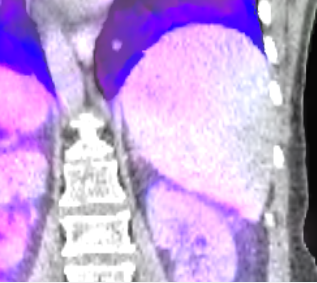

Figure 4: Coronal views with overlayed motion field to the CT data of the patient pat3D𝑝𝑎𝑡3𝐷pat3D (a-d) deformed with the model of pat4D𝑝𝑎𝑡4𝐷pat4D. The color wheel legend below indicates the direction of the motion field.

(a) First time point.

Refer to caption

(b) Second time point.

(c) Third time point.

(d) Fourth time point.

(e)